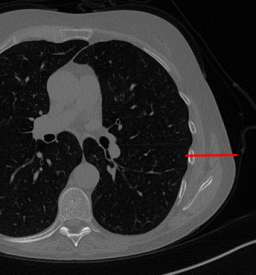

Here we present the results of RISING applied to the Mayo data set introduced in paragraph 4.1. As previously mentioned, we consider two sparse-view CT geometries, namely P360,360subscript𝑃360360P_{360,360} and P360,180subscript𝑃360180P_{360,180}. In Figure 4 we report the results for the P360,360subscript𝑃360360P_{360,360} protocol, achieved on one image of our test set. The top-left image represents the xRIS=x(15)subscript𝑥𝑅𝐼𝑆superscript𝑥15x_{RIS}=x^{(15)} reconstruction. Even if only a small number of iterations are performed, the main structures of the abdomen are visible; however, the image is still blurry. In the xISsubscript𝑥𝐼𝑆x_{IS} image, shown in the upper-right corner, we notice that the TV regularizer has acted to totally eliminate the artifacts and noise, improving the uniformity of the image in the inner structures. When compared to the ground-truth solution in Figure 2, the contours of the details in xISsubscript𝑥𝐼𝑆x_{IS} appear slightly jagged, differently from xGTsubscript𝑥𝐺𝑇x_{GT} where they are neat but, usually, corrupted by artifacts. The bottom row of Figure 4 shows the two xLPPsubscript𝑥𝐿𝑃𝑃x_{LPP} and xINGsubscript𝑥𝐼𝑁𝐺x_{ING} images, respectively from left to right. It is evident that xLPPsubscript𝑥𝐿𝑃𝑃x_{LPP} has retrieved many details but it presents noisy components, reflecting the features of its target image xGTsubscript𝑥𝐺𝑇x_{GT}. Our solution xINGsubscript𝑥𝐼𝑁𝐺x_{ING} is less corrupted, since the low-contrast regions are correctly preserved and the noise is not visible. These observations are confirmed by Figure 5, which plots the intensity profiles taken over the red line in the second crop (Figure 2). In our approach (on the right) the CNN has accurately learnt the f𝑓f map of (8) and the xINGsubscript𝑥𝐼𝑁𝐺x_{ING} red profile mostly overlaps the black one. On the contrary, the xLPPsubscript𝑥𝐿𝑃𝑃x_{LPP} profile (on the left) is more distant from its target reference.

Figure 4: Results on a test image from the Mayo data set, under the P360,360subscript𝑃360360P_{360,360} CT protocol. Top-left: xRISsubscript𝑥𝑅𝐼𝑆x_{RIS}; top-right: xISsubscript𝑥𝐼𝑆x_{IS}; bottom-left: xLPPsubscript𝑥𝐿𝑃𝑃x_{LPP}; bottom-right: xINGsubscript𝑥𝐼𝑁𝐺x_{ING}.

Figure 5: Intensity profiles taken on the horizontal red line depicted in 2, on the reconstructions in Figure 4. Left: the black and red lines are the profile relative to xGTsubscript𝑥𝐺𝑇x_{GT} and xLPPsubscript𝑥𝐿𝑃𝑃x_{LPP} respectively. Right: the black and red lines are the profile relative to xISsubscript𝑥𝐼𝑆x_{IS} and xINGsubscript𝑥𝐼𝑁𝐺x_{ING} respectively. In both the plots, the blue line corresponds to the profile on the starting xRISsubscript𝑥𝑅𝐼𝑆x_{RIS} image.